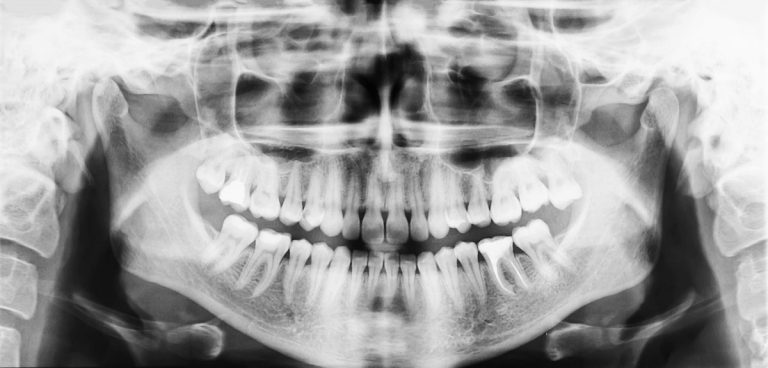

Co se děje s našimi zuby, když spíme: Sliny nemohou plnit svou funkci, bakterie mají hostinu

Za běžného režimu máme pusu zavřenou a sliny uvnitř úst plní ochrannou funkci. Přes noc se ovšem začne dít nespočet zajímavých věcí.

„Když spíme, množství slin se snižuje a současně houstnou,“ vysvětluje zubařka, ortopedka a implantoložka Dr. Yuliana Romanova. Dalším důvodem pak může být zvyk spát s otevřenými ústy. Případně vás k tomu donutí potíže s dýcháním nosem. „Když v noci klesne množství slin, jejich ochranná funkce se zhoršuje. Imunoglobuliny, které bojují s bakteriemi uvnitř úst, v této době nevznikají.“ Přitom ovšem v ústech stále dochází k aktivitě bakterií.

Podle toho, jak často a důkladně si čistíte chrup a ústa, sídlí na každém vašem zubu 1 000 – 100 000 bakterií. Jakmile usnete, jedinou jejich starostí je najít jakékoli jídlo. Protože jde o mikroskopické organismy, hodují na miniaturních zbytcích jídla, které zůstaly mezi zuby nebo na okraji dásní. A přestože už samotná přítomnost bakterií v ústech nezní moc přívětivě, věci budou ještě horší. Protože všechno, co se nají, musí také vylučovat. A bakterie nejsou výjimka.

Jejich výkaly jsou ovšem velmi kyselé. Natolik, že poškozují sklovinu na vašich zubech, čímž přispívají k jejich rozpadu i zánětům dásní. Tyto bakterie navíc nelze z úst zcela odstranit, můžete jen podniknout kroky k redukci jejich populace. Právě v zájmu takového stavu si před spaním zuby pečlivě čistěte a nezapomeňte na dentální nit. Čím méně jídla bakterie mají, tím méně jich přežije a bude takto škodit. Není to ovšem jediná věc, která se v puse děje.

Za bdělého stavu neustále polykáme sliny, ve spánku k tomu nedochází. V noci jich vzniká méně, takže bakterie a další organismy mohou celkem nerušeně prospívat. Jestli se vzbudíte a páchne vám z úst, může za to právě absence slin. To dovolilo bakteriím, aby přes noc svou populaci klidně znásobily. Podle výzkumů skřípe 8 % dospělých ve spánku zuby, jde o sklon odborně zvaný bruxismus. U dětí je to dle rodičů dokonce jedna třetina.

Nedává-li se na tuto aktivitu pozor, může vést i k velmi vážným potížím. Pokud totiž skřípete zuby, můžete ovlivnit jejich tvar, obrousit si sklovinu (enamel) nebo se kousnout do tváře. Stejně tak zvyšujete svou citlivost na horké a studené vjemy. Kromě vlivu na zuby vás to taky může vzbudit uprostřed noci, což narušuje váš spánkový režim. A protože tento pohyb vyžaduje svalovou aktivitu, nejspíš trpíte bolestmi čelisti, tváře nebo krku.

Tohle je několik důvodů, proč zvláště před spaním ústní hygienu neodbývat. Jde totiž prakticky o vaše jediné nástroje, jak aspoň nějak ovlivnit noční aktivitu ve vašich ústech. Stav chrupu také negativně ovlivňuje to, pokud v noci nespíte. Obvykle totiž něco zakusujete a málokdy se jedná o zdravý salát. Jde o nějaké brambůrky, sladkosti a podobné pochoutky. U lidí s tímto režimem dochází častěji k rozvoji cervikálního kazu.

Procesy pak probíhají – kvůli menšímu slinění i změně složení slin – ještě rychleji. Jakékoli samočištění je pro tělo velmi náročné. Nemluvě o tom, že noční pochutiny jsou často zapíjeny sladkými šumivými nápoji, které zdraví také dvakrát neprospívají. Těsně před spaním je proto ideální nekonzumovat nic.